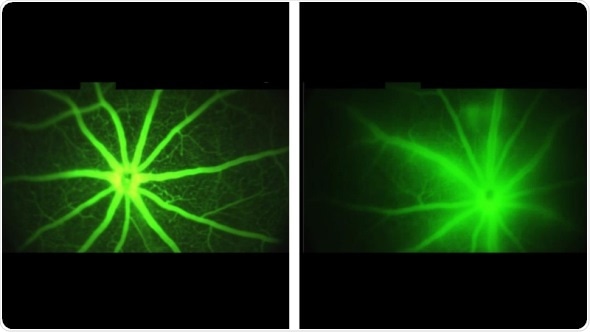

Images of the mouse retina with a fluorescent fluid tracer. Diseased blood vessels allow the tracer to permeate nearby tissues. Vessels treated with AXT107 do not allow fluids to escape and exhibit clean crisp borders with surrounding tissue. Credit: Alexsander Popel

The researchers next wanted to see if the same effect could be achieved in living blood vessels. They used a fluorescent dye to observe the blood vessels in the eyes of normal mice and mice genetically engineered to mimic human macular degeneration. In the healthy mice, the researchers observed glowing blood vessels with crisp edges and very little fluorescence outside of the vessel. However, in the mice with macular degeneration, glowing liquids passed through the blood vessels, blurring the barrier between blood vessels and the surrounding tissues.

The researchers treated the engineered mice with leaky blood vessels, like those seen in macular degeneration, with injections of the AXT107 peptide into the animals’ eyes. After four days, the researchers found that in mice treated with AXT107, about half as much of the fluorescent dye leaked from their vessels as in animals that received saline injections containing no drug. These results, say researchers, show that the AXT107 drug was able to seal up leaking vessels and prevent vision-blocking fluids from permeating into the surrounding tissue.